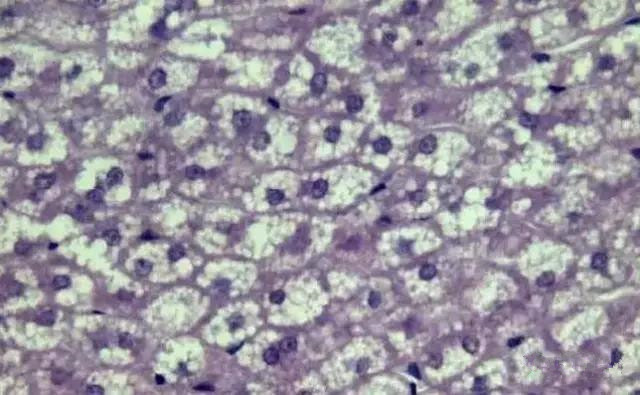

“ 脂肪变性

“ 肝脂肪空泡

肝细胞内甘油三脂蓄积过多为主要病理变化。脂肪肝病已成为水产养殖业的一大难题。